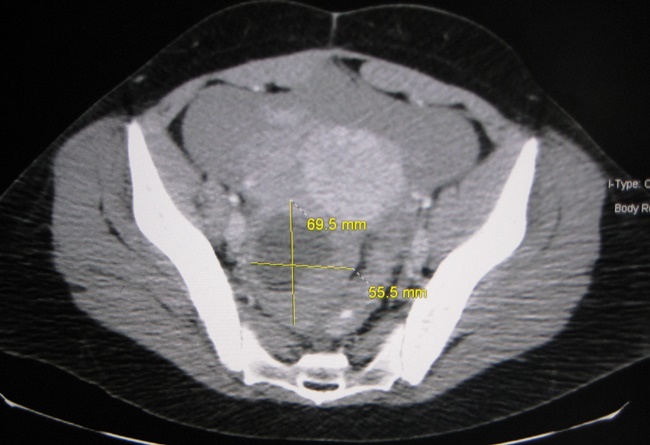

3. หากเกิดกรณีไข่ตก แต่เราไม่ได้ตั้งครรภ์ แล้วซีสต์นั้นไม่ยอมหยุดสร้างฮอร์โมนโปรเจสเตอโรน จะทำให้มีปัญหามากมายตามมา ซึ่งถ้าซีสต์นั้นมีขนาดใหญ่มาก หนักมาก หรือที่เราเรียกว่า “เดอร์มอยด์ซีสต์” จะทำให้รังไข่เกิดการบิดตัวจนเลือดไม่สามารถไหลไปหล่อเลี้ยง สุดท้ายก็กลายเป็นความเจ็บปวด

4. นอกจากนี้ยังมีปัญหาเกี่ยวกับซีสต์อีกอย่างคือ ซีสต์ที่รังไข่สร้าง บางครั้งมันไม่ได้โตและหนักมากแค่ถุงเดียว แต่ใหญ่และหนักหลายถุงพร้อมกัน เราเรียกว่า “ภาวะถุงน้ำรังไข่หลายใบ” โดยมีสัญญาณบอกใบ้อาการหลายอย่าง เช่น สิวขึ้นเยอะ ผมยาวเร็วมาก รอบเดือนยาวนานและถี่กว่าปกติ อ้วน ซึ่งเราสามารถรักษาได้ด้วยการออกกำลังกายและการลดน้ำหนัก รวมถึงการทานยาต่างๆ ตามที่คุณหมอสั่งให้ด้วย